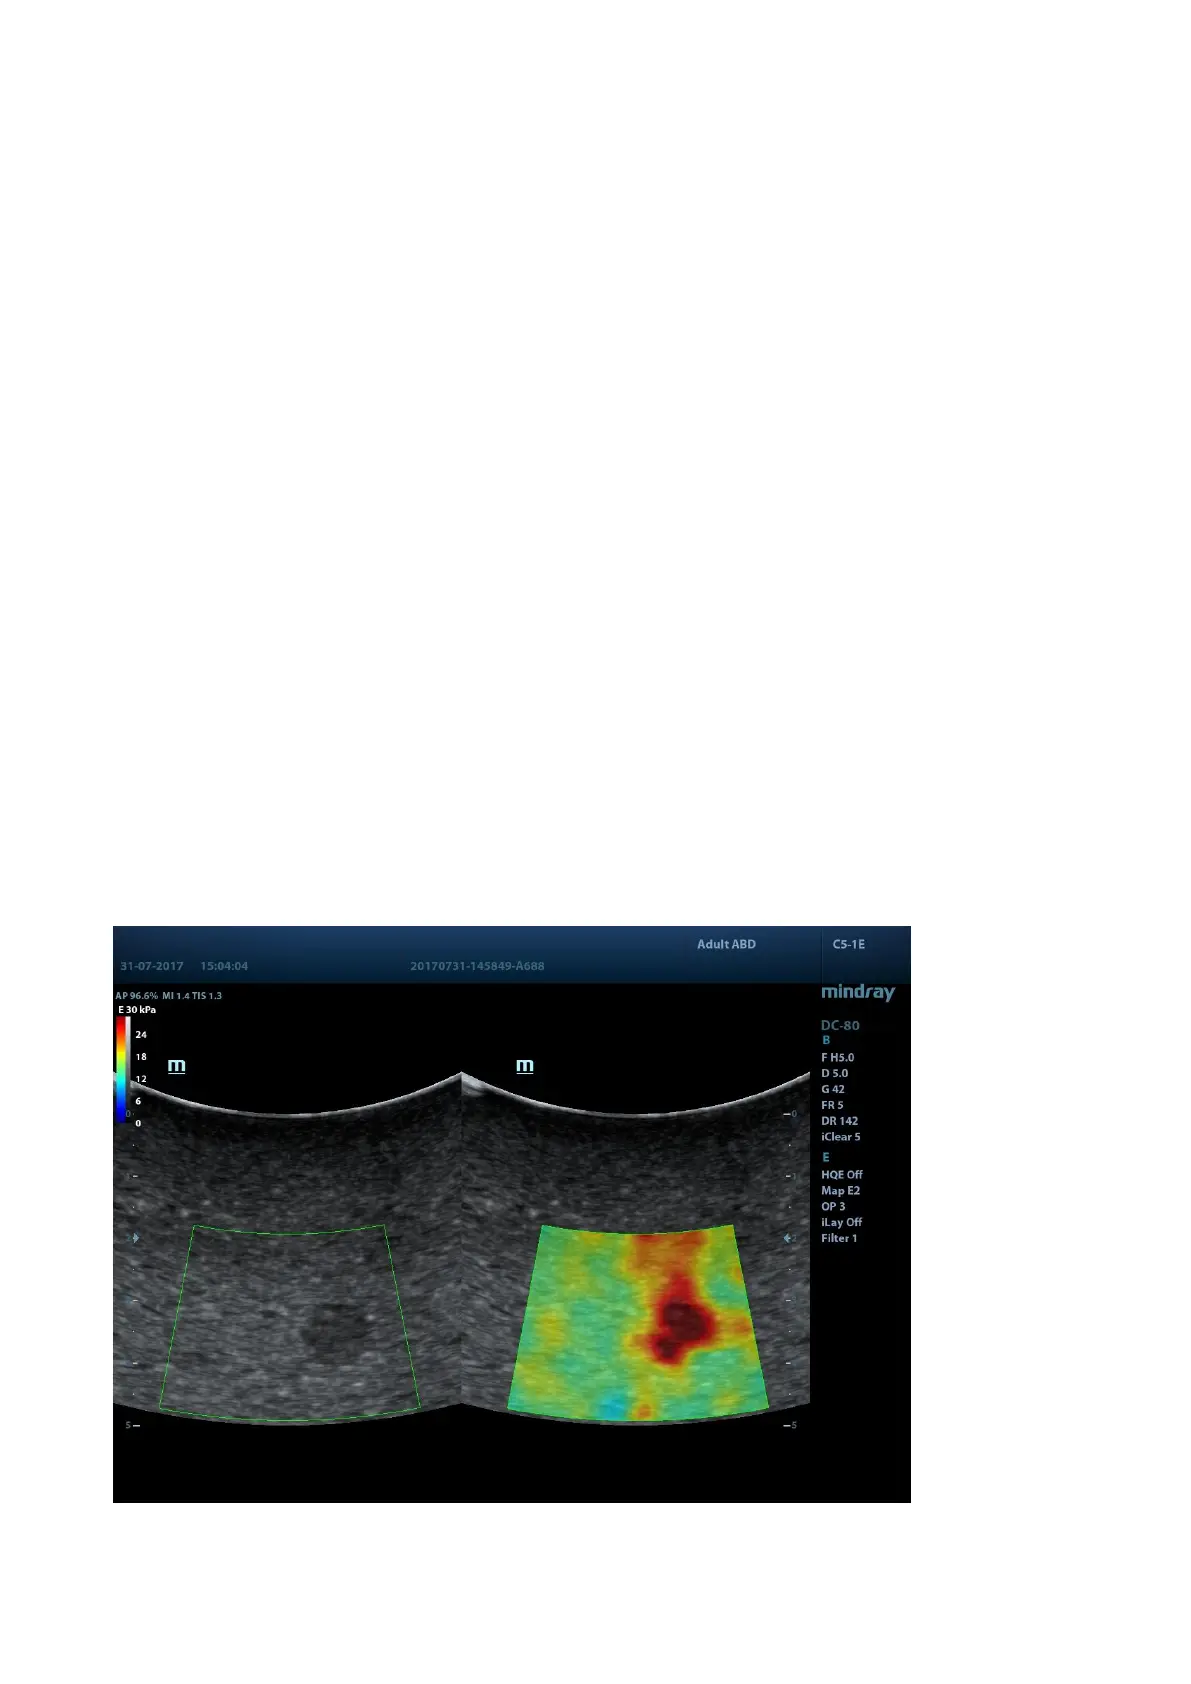

5.13.2 STE Imaging (Sound Touch Elastography)

Keep the probe still to produce the elastography image in real-time 2D mode. The tissue hardness

of the mass can be determined by the image color and brightness. Besides, the relative tissue

hardness is displayed in quantitative manners.

STE imaging provides you real elasto modulus for quantification analysis without relying on

technique.

The SC5-1E and C5-1E probes support the STE imaging in Adult ABD, Ped-ABD, ABD-Difficult,

EM ABD, EM FAST exam modes.